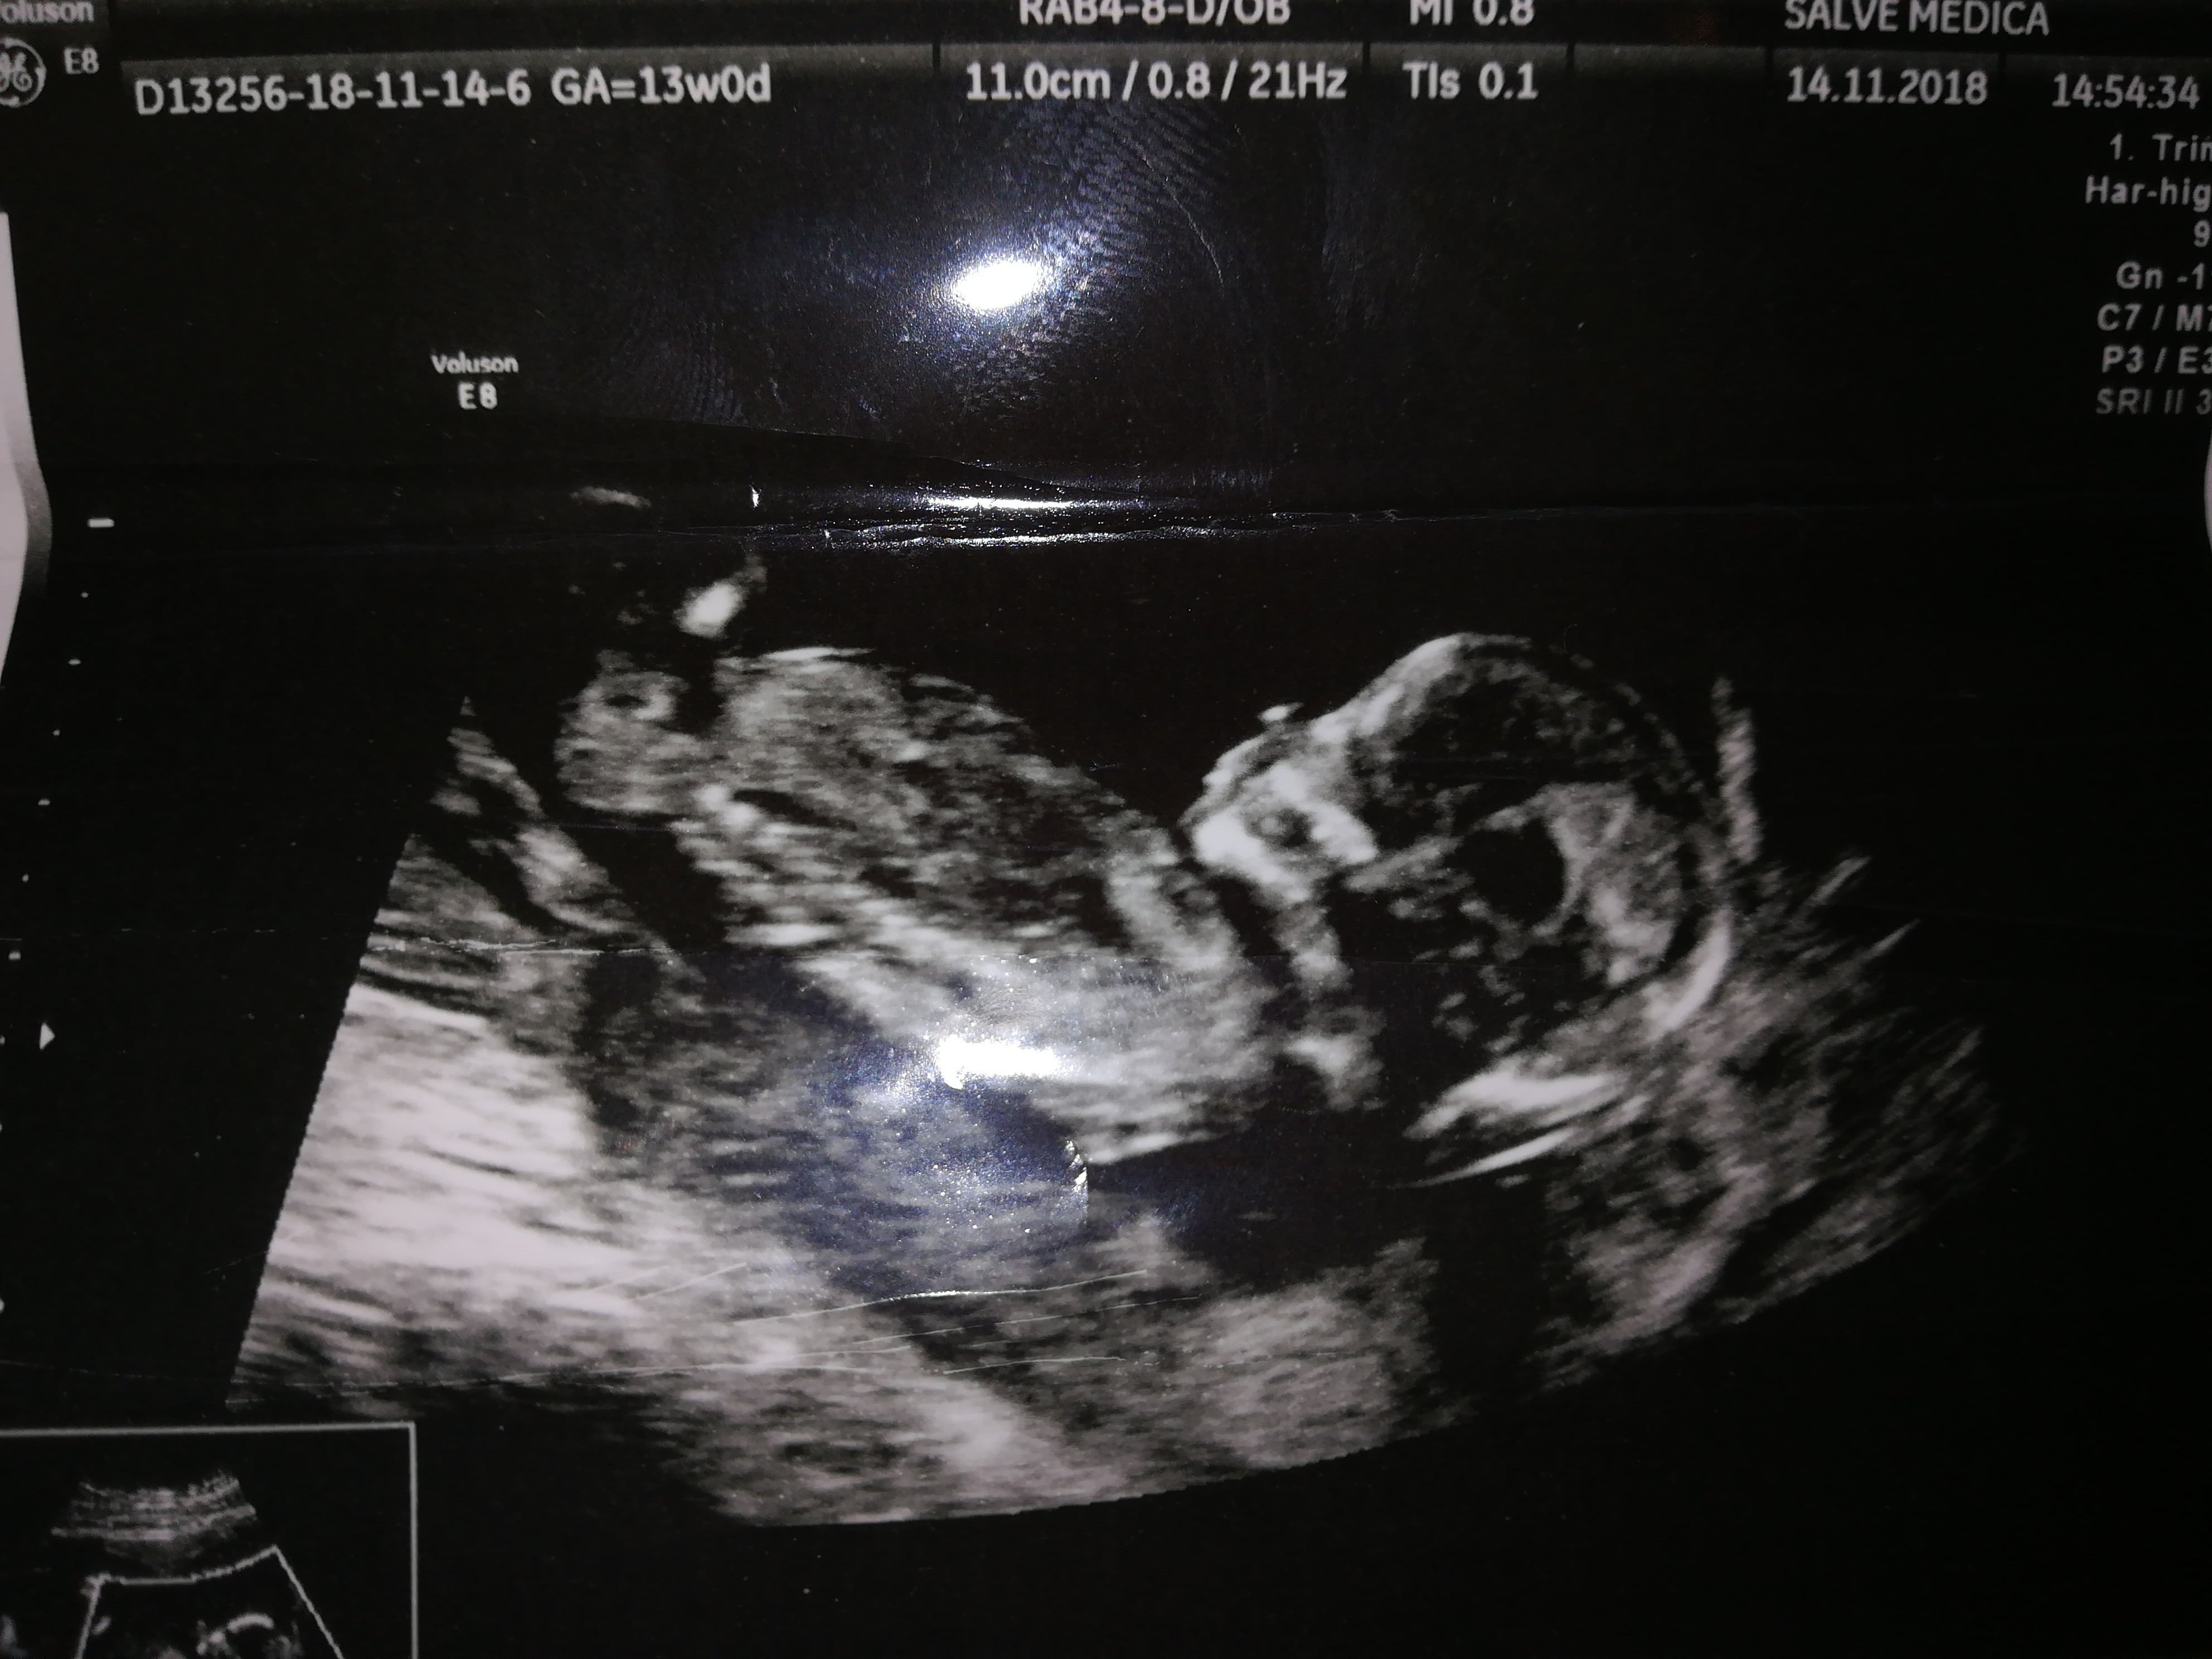

Hej dziewczyny,

A powiedzcie co u mnie?

Z 13tyg na podstawie wyrostka - szansa na dziewczynkę, ale dzidzia w ogóle się nie chciala pokazać...

17 tydzien- chłopak, no widać widać...

Ale myślicie że to może być jednak pepowina, lub coś innego...I bedzie dziewczynka hmm?

Proszę Was o opinie ;)

Mamy już jednego chłopca, maz liczy na dziewczynkę, ja widzę chłopca no ale...;)